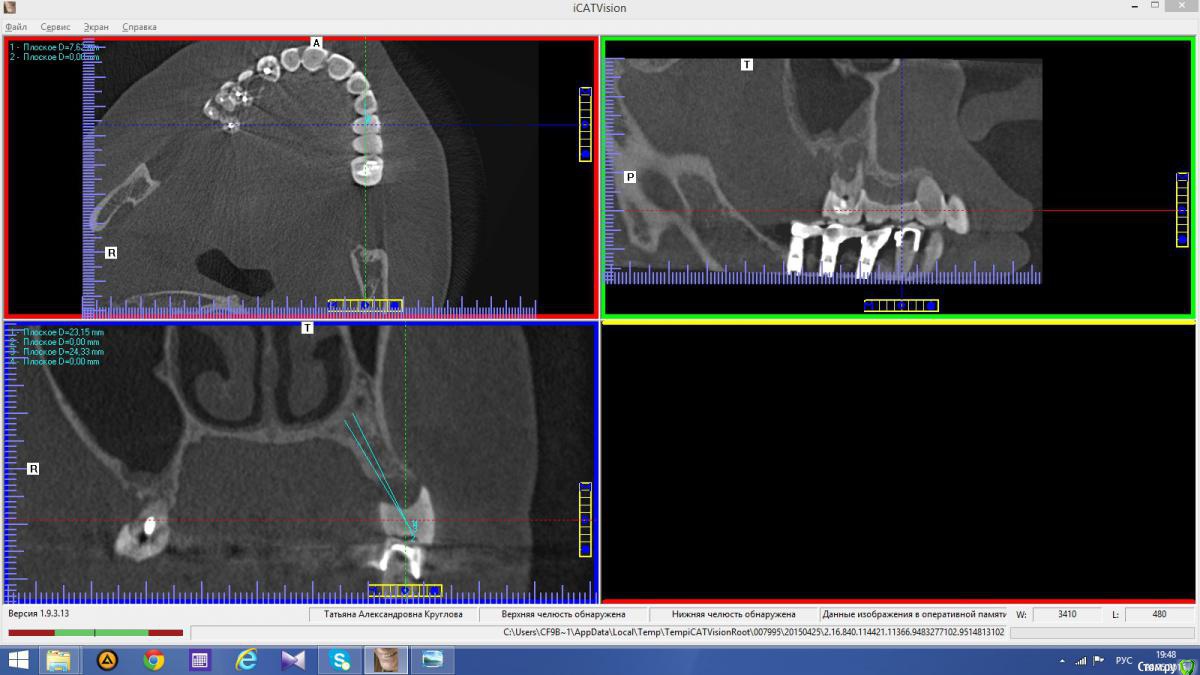

Abuk Опубликовано 24 ноября, 2015 Автор Поделиться Опубликовано 24 ноября, 2015 Снимки не могли бы показать? .все что есть готовое. Ссылка на комментарий

Abuk Опубликовано 24 ноября, 2015 Автор Поделиться Опубликовано 24 ноября, 2015 (изменено) Радикально Вы. Что оставили ей после имплантации-это инд аббатменты? На них мокап одели и нагрузили сразу? У всех был торк хороший? Или это временные абб? Что за систему использовали? В планах консоль назад, правильно я понимаю?Спасибо.увидев такую работу,сам так же подумал бы). Но там подвижность 2-3 ст. ближе к 3. Мосты болтались ,2 ки в хлам. 1 ки только стабильны. Снимал мосты,проводил кюретаж. Решил дернуть.Абатманы временные, тех. сделал на них коронки. Система анкилоз. Работа,на посл. фото, постоянная . Имплы в области 4 и по одному моляру ,консоли. Мок ап был до имплантации . По нему шаблон. Стабильность 15 -20 на 23 , остальное больше 30. Изменено 24 ноября, 2015 пользователем Abuk 1 Ссылка на комментарий